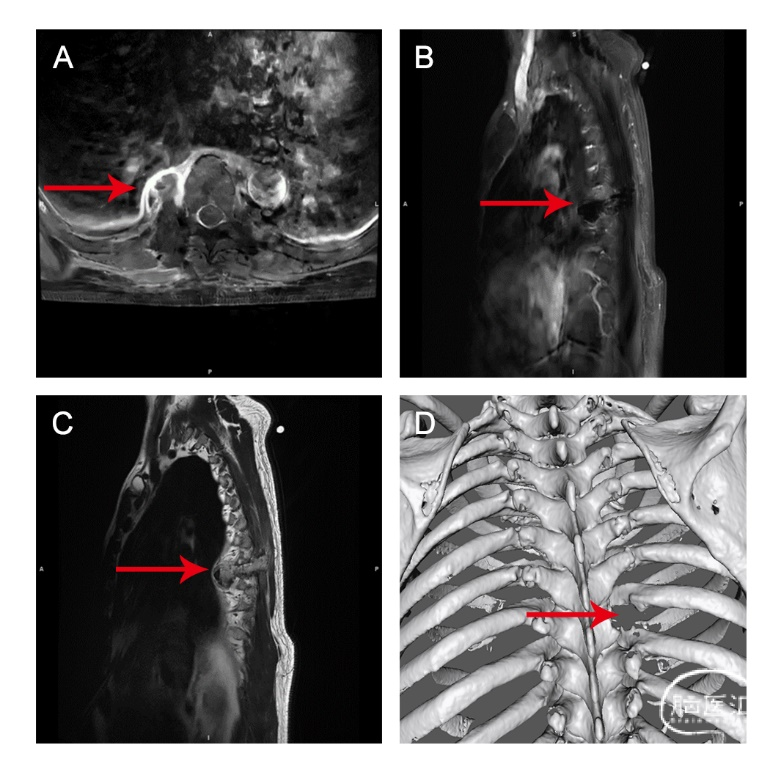

患者男,64岁,体检发现胸腔内椎旁占位1年,无神经体征,术前MRI显示T8椎旁占位。

术后MRI显示肿瘤完全切除,三维重建图像显示了切除后的骨性结构。